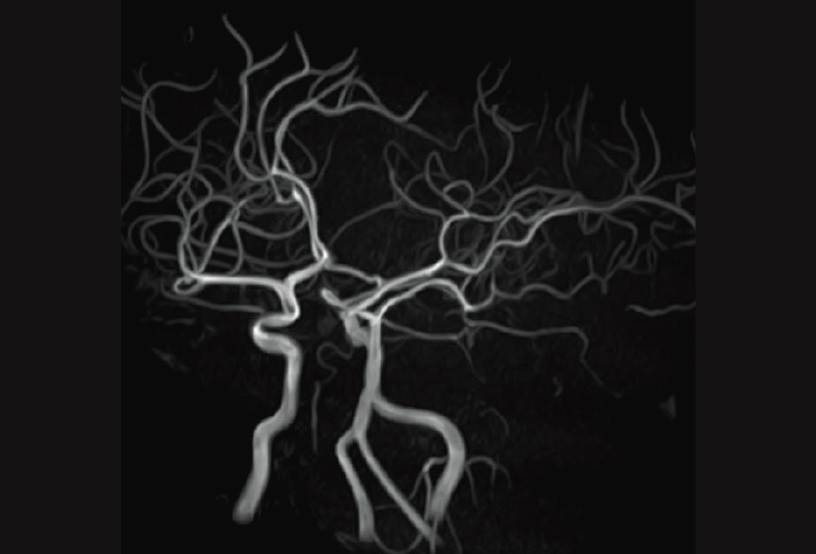

RADAR’ın TOF MRA ve GrE T2*WI’deki etkileri

RADAR, yüksek hassasiyetli sinyal düzeltme teknolojisi kullanılarak GrE sekanslarına uygulanmıştır. Bu, rutin baş incelemelerinde gerekli tüm sekanslar için RADAR’ın kombine kullanımını mümkün kılmıştır.